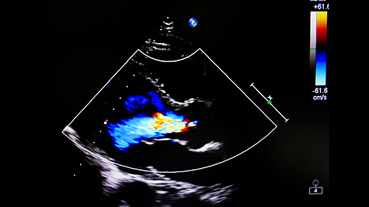

In 2025, cardiologists and cardiac surgeons at NewYork-Presbyterian led breakthroughs that impacted a range of diseases and conditions from advanced heart failure to pediatric valve disease. Physicians and researchers from Columbia and Weill Cornell Medicine pioneered the use of artificial intelligence to identify structural heart disease, launched a mobile app to expand access to heart failure education, performed one of the first split-root domino partial heart transplants, and more. Our experts remained at the forefront of innovative, multidisciplinary care, delivering comprehensive treatment for the most complex cardiac diseases.

Our world-renowned Columbia and Weill Cornell Medicine physicians and surgeons in our comprehensive cardiology, heart surgery, and vascular programs spearhead groundbreaking clinical and scientific research and provide the most innovative treatments to optimize patient outcomes for all stages of disease complexity. Our clinicians are experts in minimally invasive approaches and novel therapeutics for all types of heart disease and work across disciplines to provide compassionate care to all patients.